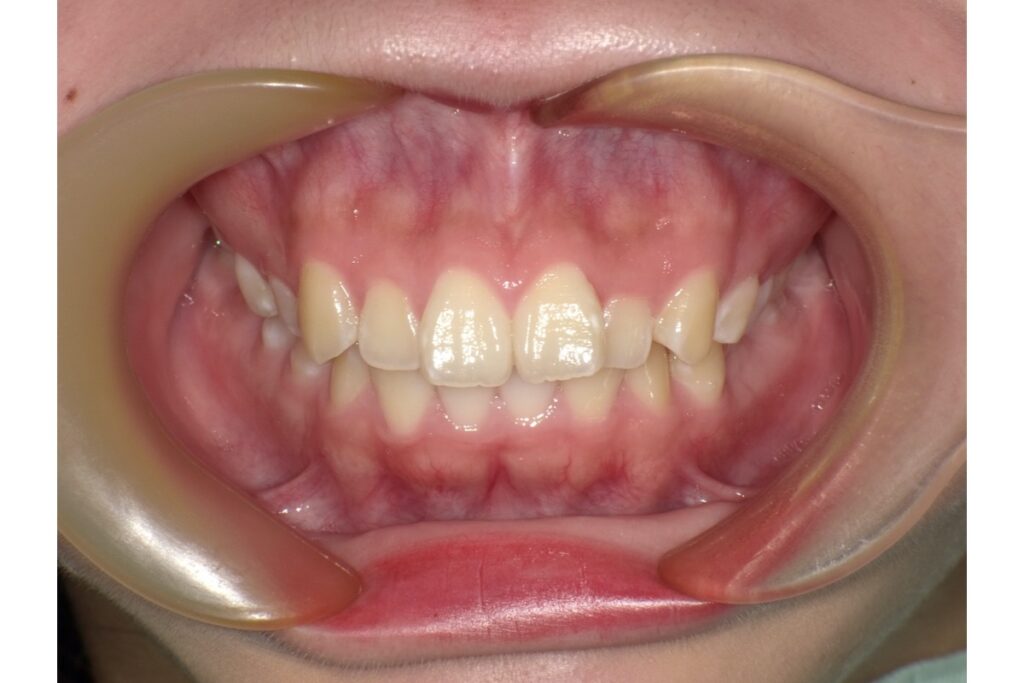

治療前

治療前後の写真を見比べると、前歯の引っ込み具合がよく分かります。

歯を抜いて治療を行っているので、横から見たときの変化がとても分かりやすいかと思います。歯だけではなく、横顔も口元がスッキリしますよ。